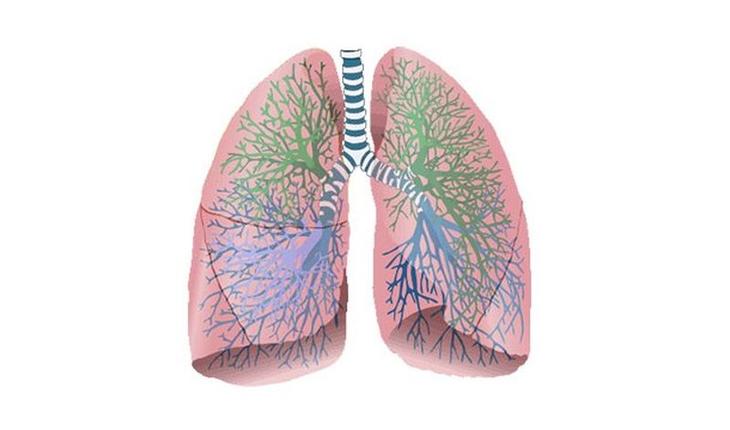

11) И даже дышим мы, как выяснятся, несколько по-разному. Мужчины получают большую часть энергии в результате анаэробного дыхания, а женщины, напротив – в результате дыхания аэробного.